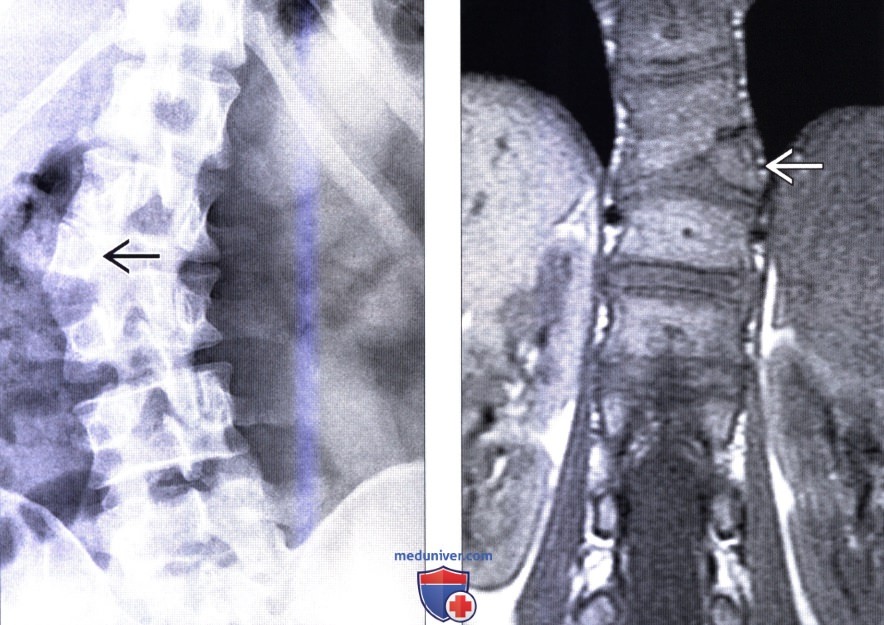

Позвонок Th10: анатомия и фото медицинских иллюстраций